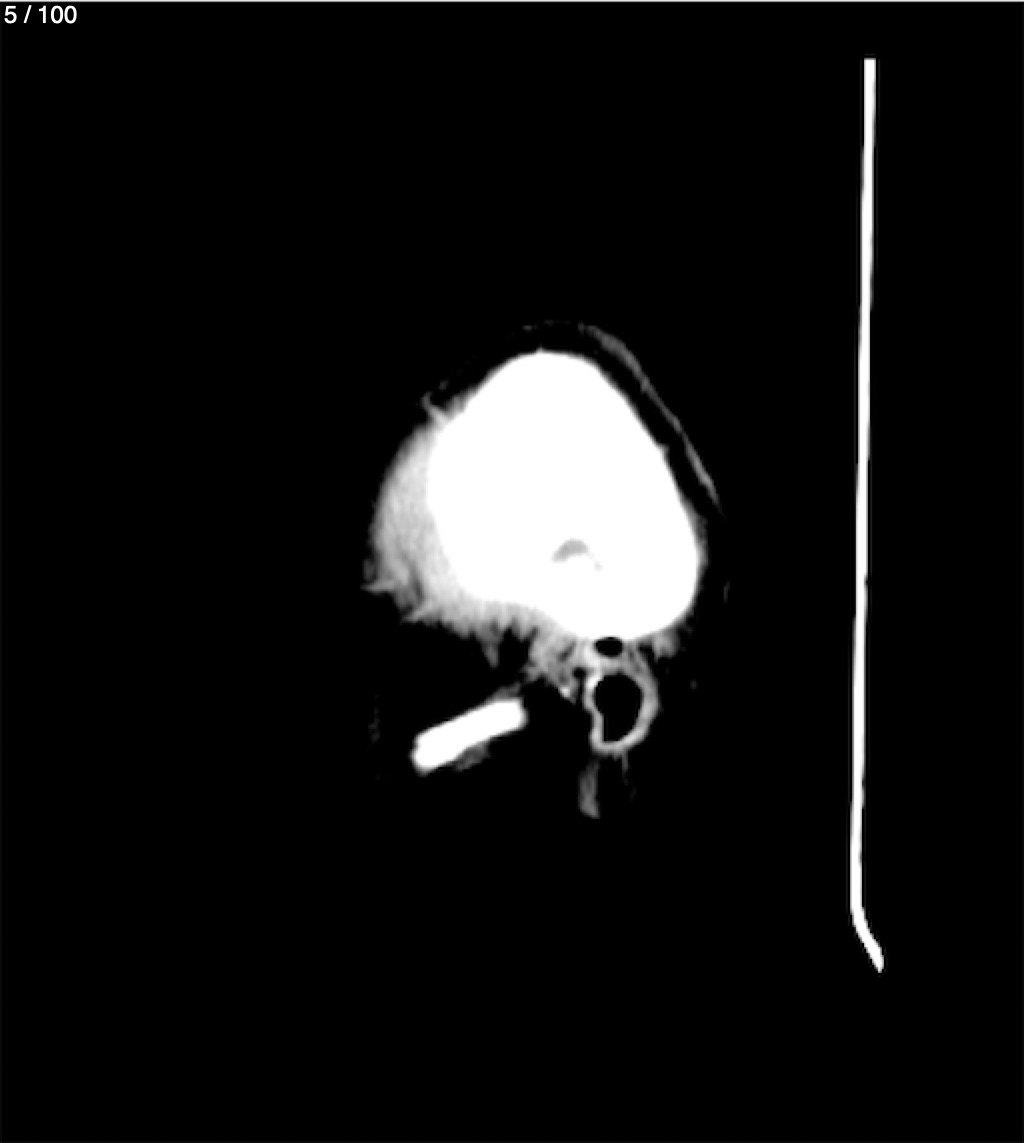

Fernando Daniel Gutierrez Caraba - Tc. Craneo Syc